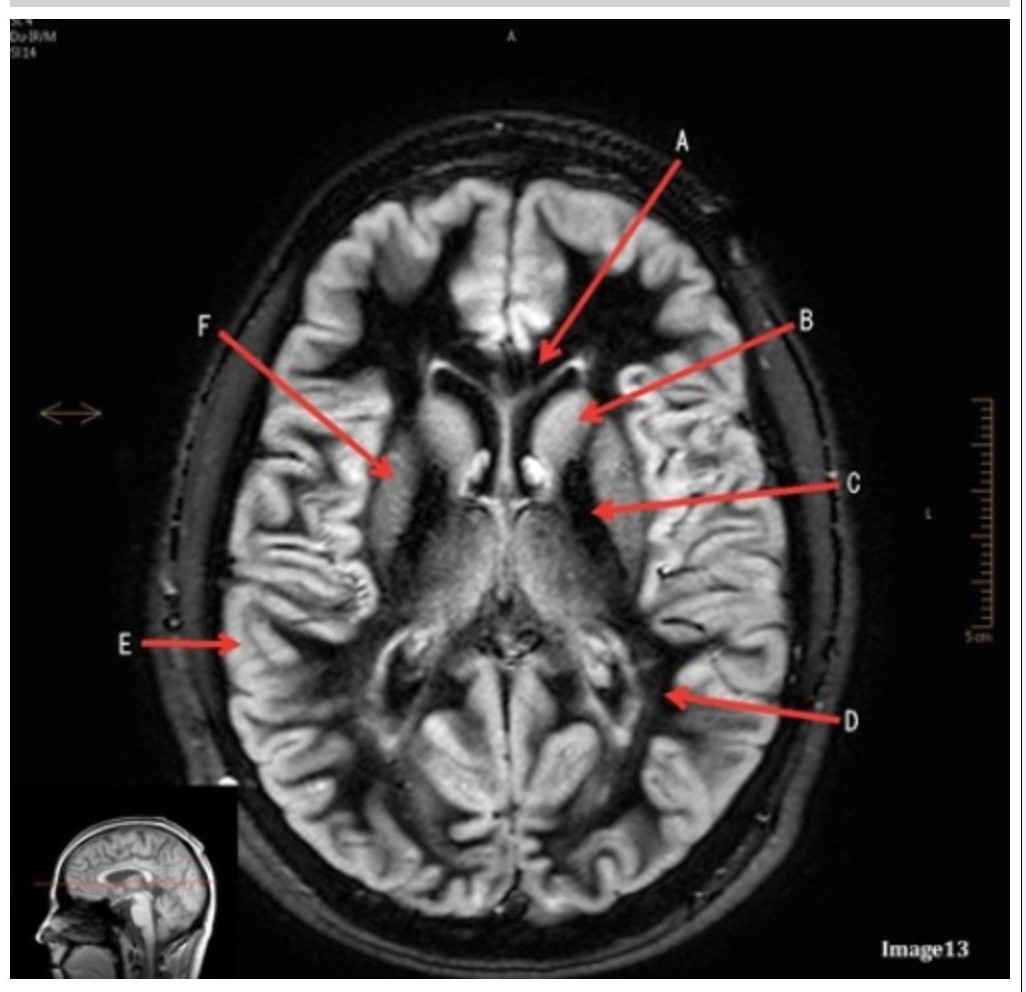

Letter E in Image 13 is pointing to:

A. Grey matter

B. White matter

C. Lentiform nucleus

D. Caudate nucleus

E. Internal capsule

Letter B in Image 13 is pointing to:

A. Splenium of the corpus callosum

B. Genu of the corpus callosum

C. Lentiform nucleus

D. Caudate nucleus

E. Internal capsule

Letter F in Image 13 is pointing to:

A. Grey matter

B. White matter

C. Lentiform nucleus

D. Caudate nucleus

E. Internal capsule

Letter D in Image 13 is pointing to:

A. Grey matter

B. White matter

C. Lentiform nucleus

D. Caudate nucleus

E. Internal capsule

Letter C in Image 13 is pointing to:

A. Splenium of the corpus callosum

B. Genu of the corpus callosum

C. Lentiform nucleus

D. Caudate nucleus

E. Internal capsule

Image 9 is an example of a _____ weighted sequence acquired in the _______ scan plane.

A. T1; Axial

B. T2 FLAIR; Sagittal

C. T2; Axial

D. T2; Coronal